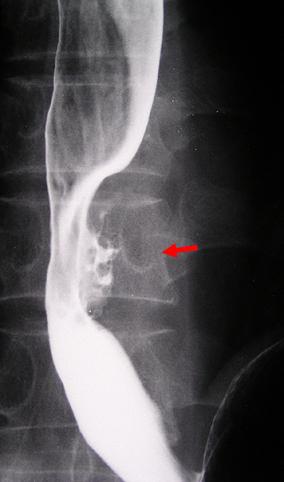

疾病(病理主体)的分类恶性上皮肿瘤/扁平上皮癌

部位(按器官分)食道/下

检查方法X线

肿瘤的肉眼分类3型(溃疡浸润型)/

肿瘤最大直径35~40

肿瘤的深度s(a)